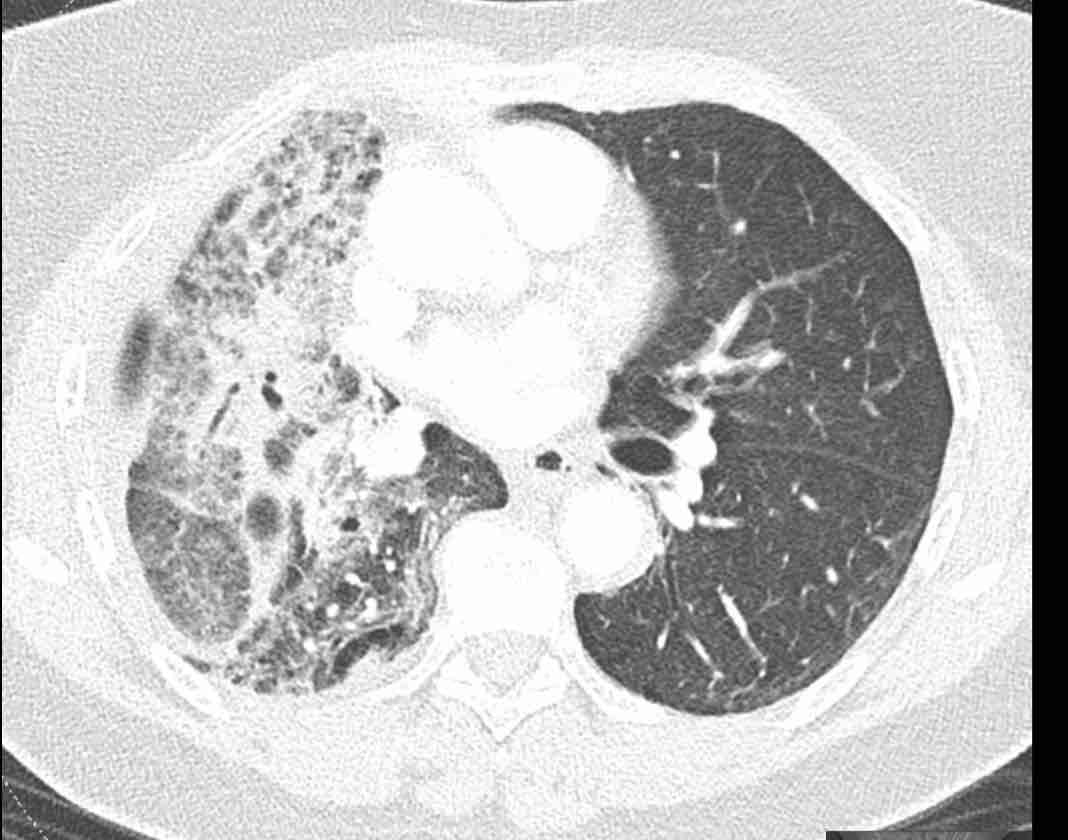

Những thay đổi cấu trúc lan rộng ở nửa ngực phải sau hóa xạ trị cho ung thư phổi không tế bào nhỏ (NSCLC) giai đoạn 4.

Theo dõi đường đi của các phế quản cho thấy thùy trên phổi phải phần lớn còn thông khí, trong khi